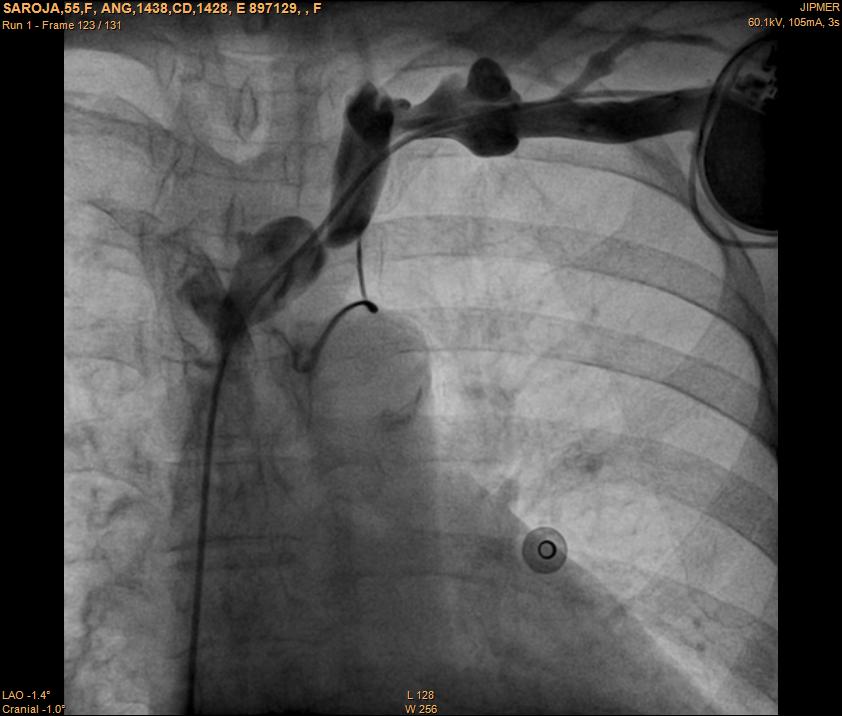

Venogram

• Difficult puncture

• Pre-existing leads

• 10-15 ml of contrast from ipsilateral arm

• Management of stenosis

Puncture with venogram